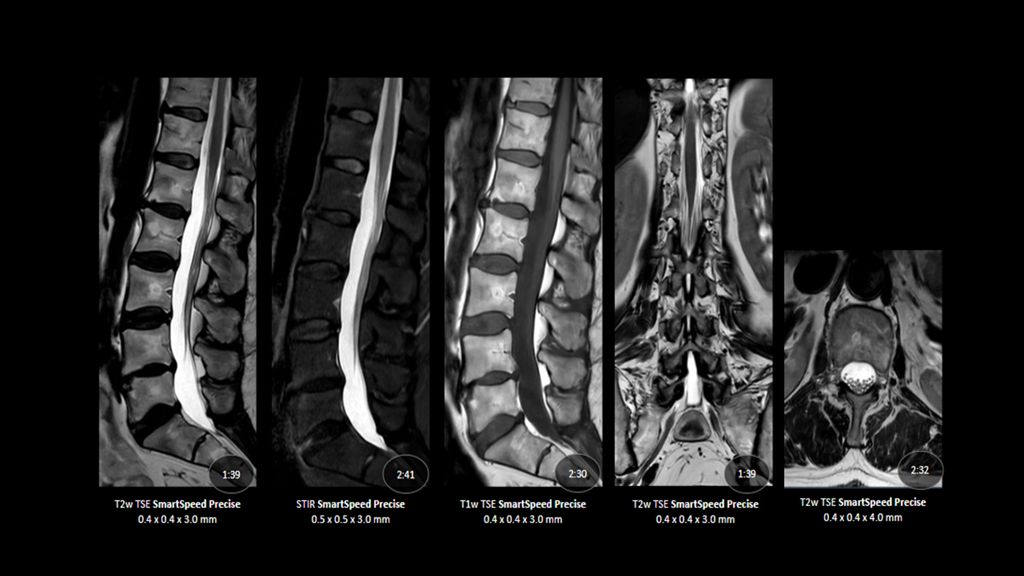

1. Compared to SENSE imaging, with no loss in image quality.

2. Reconstruction technology Compared to conventional (SENSE/ Compressed SENSE, SmartSpeed AI) imaging. Sharpness was evaluated with phantom scanning.

3. dStream based systems, not available for Prodiva and Multiva systems.